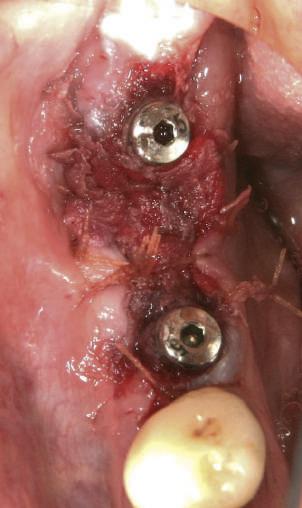

Reprepararea intraorală a bonturilor Acest pacient prezenta dentiţia maxilară compromisă, refuzând proteza mobilizabilă. Prin abordarea în etape, se menţin o parte din bonturile dentare naturale; s-a observat recesie în momentul amprentării pentru cel de-al doilea grup de implanturi.

Fig. 1 prezintă pacientul după inserarea primului set de bonturi implantare individualizate; dinţii naturali adiacenţi

sunt încă prezenţi pentru a susţine puntea provizorie.

Şapte luni mai târziu (fig. 2), acele bonturi individualizate din prima etapă au manifestat semne de recesie de 1-3mm. Atitudine: S-a decis reprepararea intraorală a tuturor bonturilor (fig. 3), astfel încât toate marginile bonturilor să fie la nivelul sau sub marginea gingivală (de notat că 1.1. şi 2.1. au fost submersaţi ulterior pentru a avea sprijin implantar deplin).

Deşi reprepararea a îmbunătăţit marcat estetica finală, a necesitat aplicarea şnurului de retracţie, amprente noi şi turnări noi.

Cazul (1): Reprepararea intraorală a bonturilor Figurile

1. Aspect după inserarea primului set de bonturi implantare individualizate.

2. După 7 luni, bonturile individualizate din prima etapă au prezentat recesie de 1-3mm.

3. Bonturile repreparate intraoral.